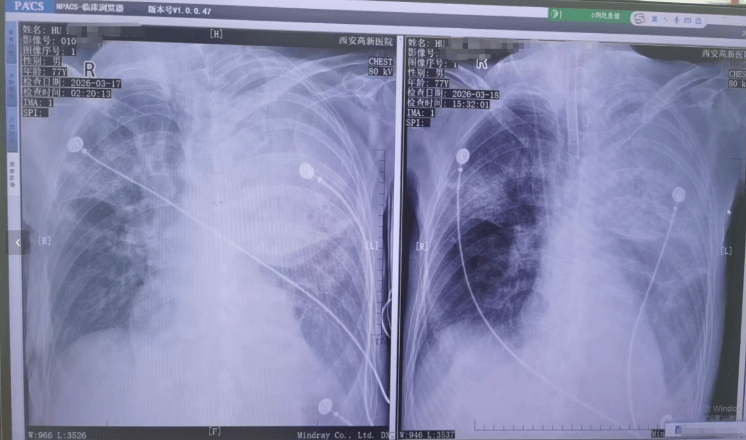

胡先生说,起初以为是感冒,住院治疗没有效果,还越来越严重,以至于病情危重,“整个肺部全白了”,并且出现呼吸衰竭,医院甚至下了病危通知书世界杯真钱开户 。3月17日,家人赶紧将父亲转院到西安高新医院抢救,到医院以后就住进了ICU。经检查,才发现是鹦鹉热衣原体感染导致的重症肺炎。胡先生提供的一份《西安高新医院诊断证明》显示,胡先生的父亲3月17日以重度肺炎入院。诊断为重症肺炎(鹦鹉热衣原体感染)I型呼吸衰竭,急性呼吸窘迫综合征,脓毒症等。

▲患者胸片